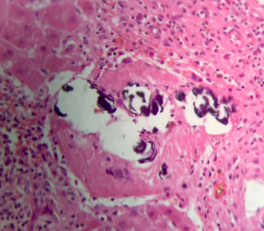

Microscopic (histologic) description

- Ova are mainly seen in the loose submucosa of large intestine, usually with formation of granulomas and infiltration by eosinophils and inflammatory cells

- Later the muscularis mucosa becomes involved and the overlying mucosa shows small superficial ulcers

- Fibrosis develops in chronic stage, when only calcified eggs are seen

Microscopic (histologic) images

Contributed by Nalini Bansal Gupta, M.D., Lisa Cerilli, M.D. and @zaalruwai83 on Twitter